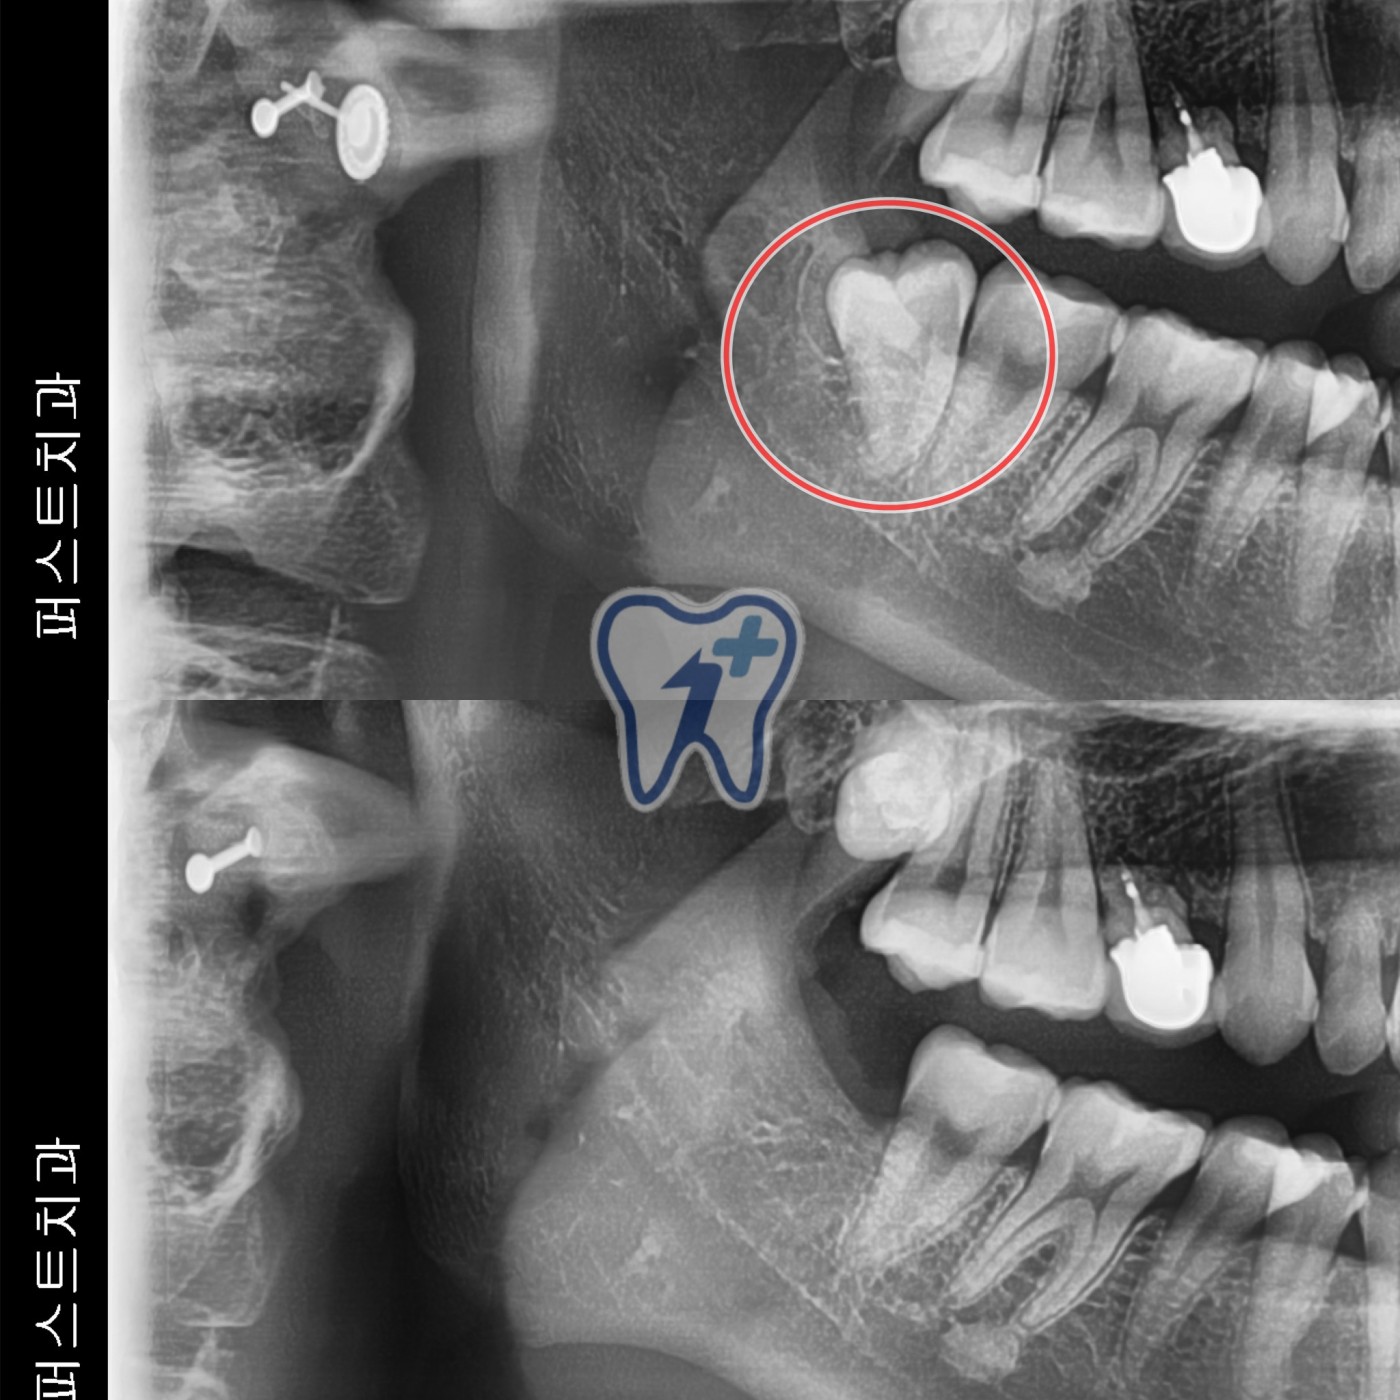

사랑니 발치 사례